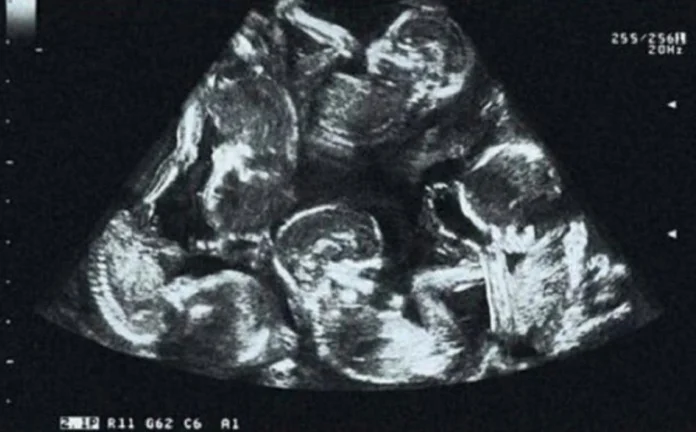

Ljekari su najprije mislili da nosi trojke, potom četiri bebe. Ali je njihov finalni zaključak bio da sretna majka nosi pet beba, budući da je njen stomak neprestano rastao.

Bez ikakvih komplikacija ona je rodila petoro zdrave djece carskim rezom, od čega četiri dječaka i jednu djevojčicu. Ovo je prvi zabilježeni slučaj u Češkoj budući da su bebe začete prirodnim putem.